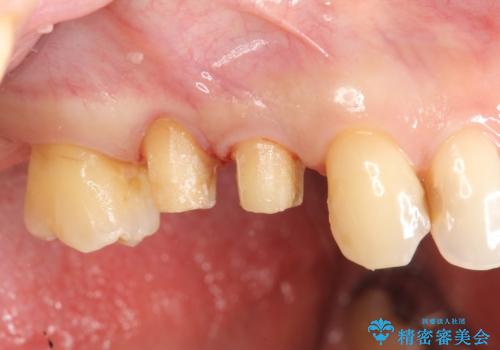

特定の歯に強く力がかかりまた歯周病により臨床歯根が短くなっているような場合、歯の動揺を抑えるため連結補綴が検討されます。

歯の動揺が続くとより周囲の骨を失い最終的には歯を喪失してしまう可能性が高くなってしまうためです。

今回連結補綴を行うにあたり、歯周病の問題を解決するために再生療法・歯周ポケット除去手術を、またより歯の神経を保存し力に対抗できる環境を整えるために小矯正を行い精度の高いメタルボンドクラウンを製作することができました。